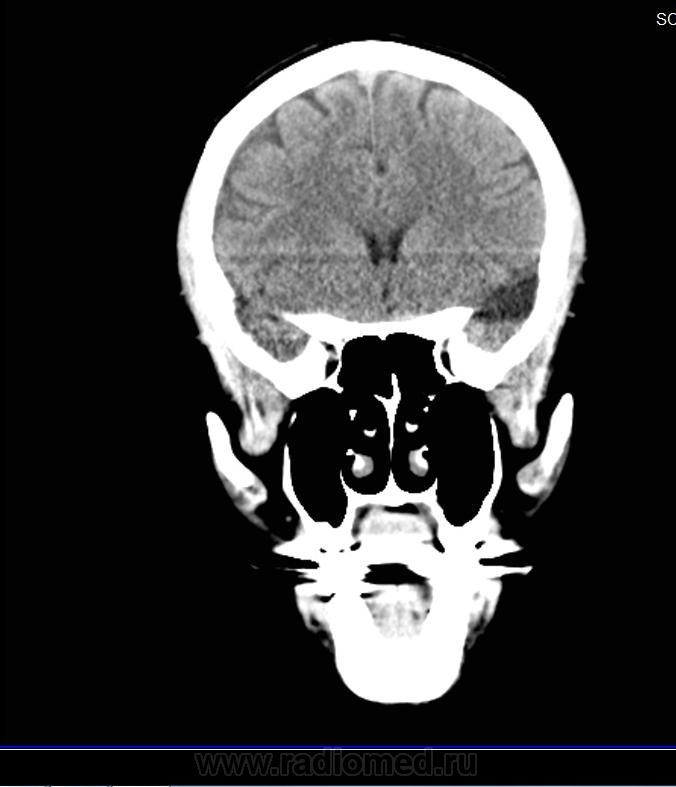

На снимках КТ головного мозга непонятное белое пятно.

Обясните мне , пожалуйста, что это за белое пятно, темное возле шеии, и засветленное пятно сверху?

Диагноз : Ушибленная рана затылочной области.  В левой лобной доле базально зона ушиба мозга -3 х 2.5 х 1 см.

Эта КТ  сделана через сорок дней после травмы. Доктор сказал, что все нормально, но до сих пор чувствую себя неважно.

Трудно понять текст непрофессионала, но предположу, что "темное возле шеии" - это жировая ткань, "засветленное пятно сверху" - это эпифиз, а  "что это за белое пятно" - дажене представляю к чему относится.

Обызвествление шишковидной железы.

Скорее обызвествление сосудистого сплетения желудочка.

Для железы далековато, а для заднего рога бокового желудочка- самый раз.

Да, вы правы, далековато от средней линии